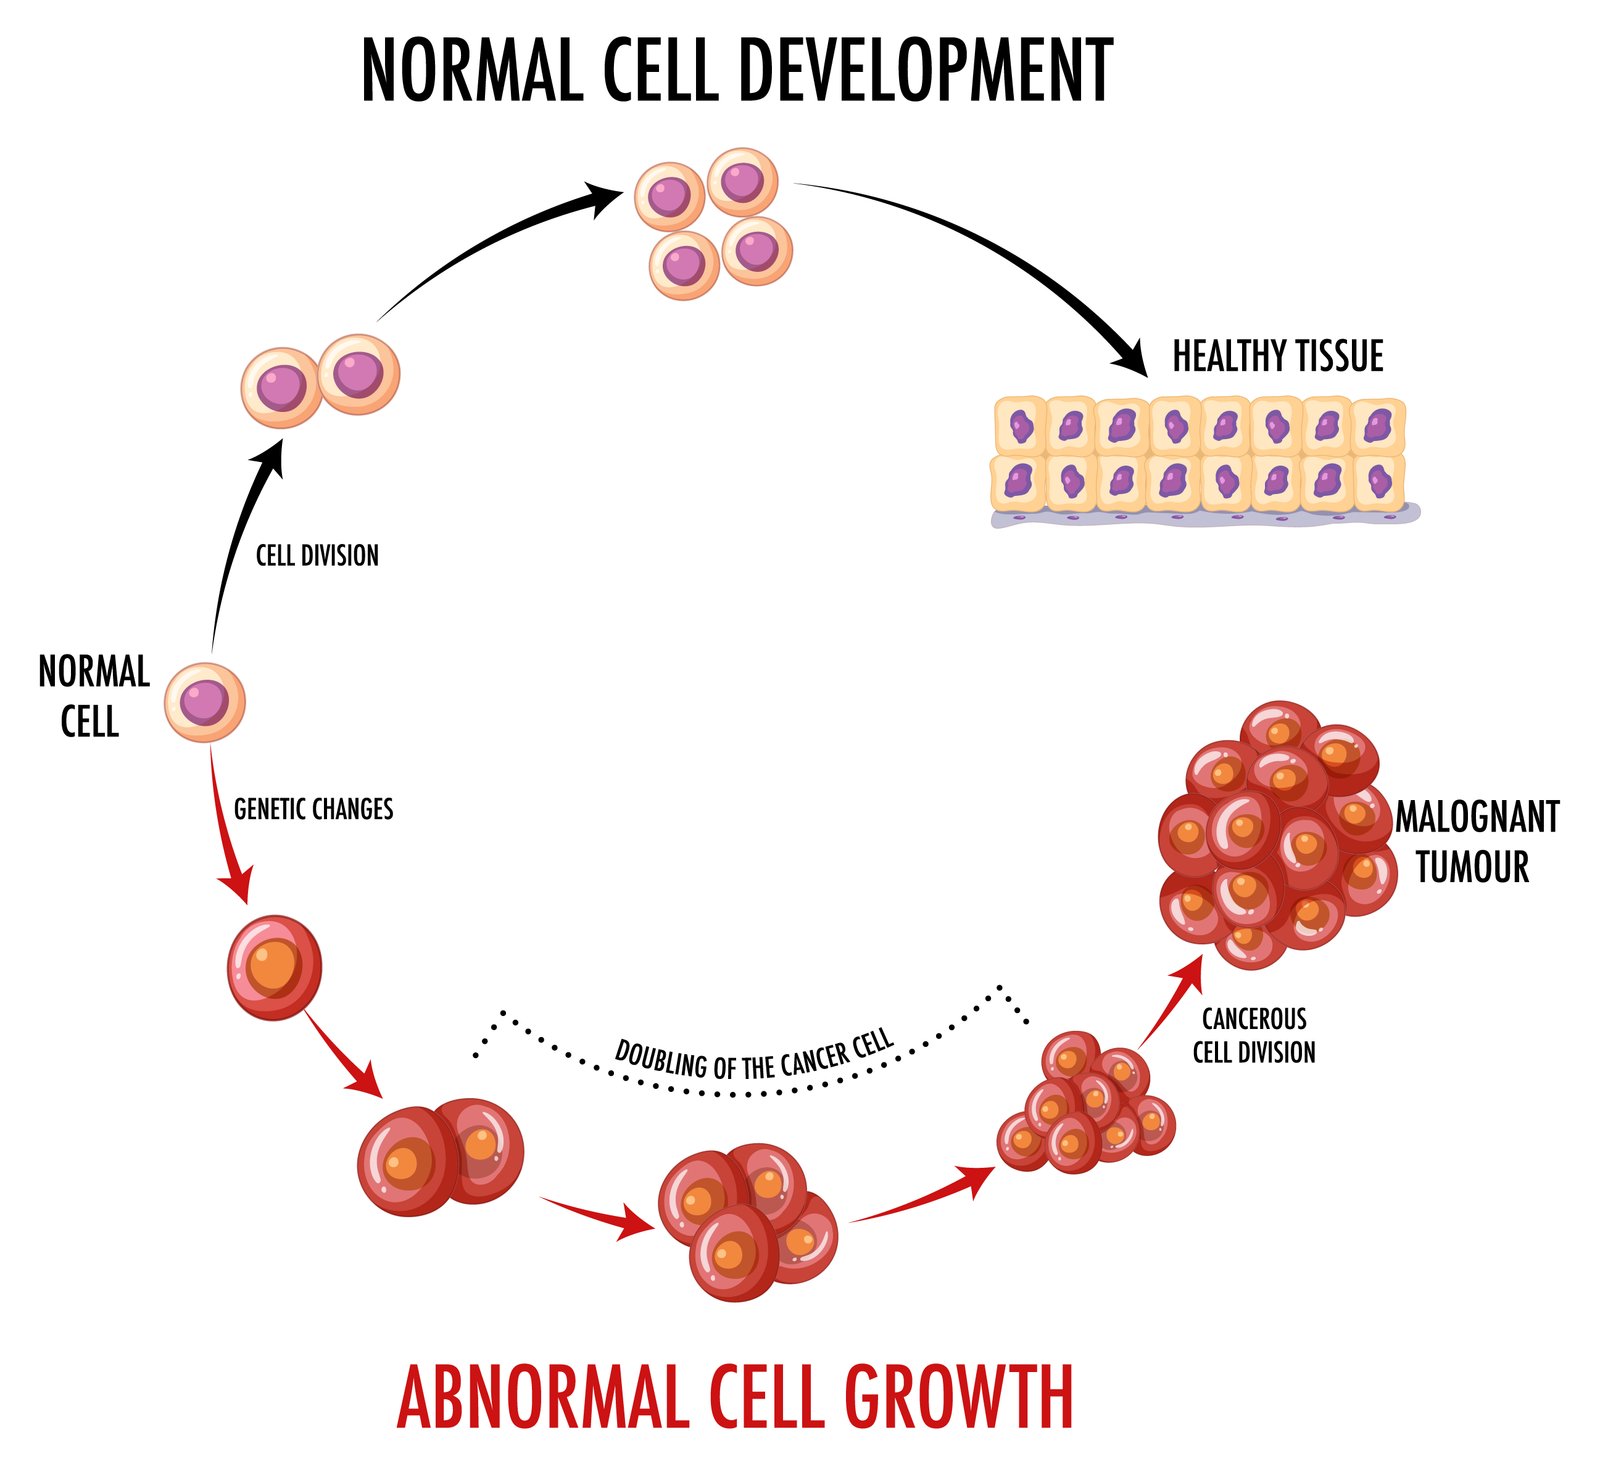

What Is Stem Cell Therapy

Stem cell therapy is a path to recovery, not an instant cure. At QA Stem Cell Center, we support patients throughout their journey, from consultation to follow-up care.

Mesenchymal stem cells (MSCs) are the workhorses of this therapy, possessing unique properties that make them ideal for treating various medical conditions. These cells have the remarkable ability to:

- Differentiate into various cell types

- Modulate the immune system

- Reduce inflammation

- Promote tissue repair

By harnessing these capabilities, stem cell therapy offers hope for patients who have not found relief through traditional medical treatments.

How Stem Cell Therapy Works?

The process of stem cell therapy at QA Stem Cell Center is both sophisticated and personalized. Here’s a breakdown of how it works: